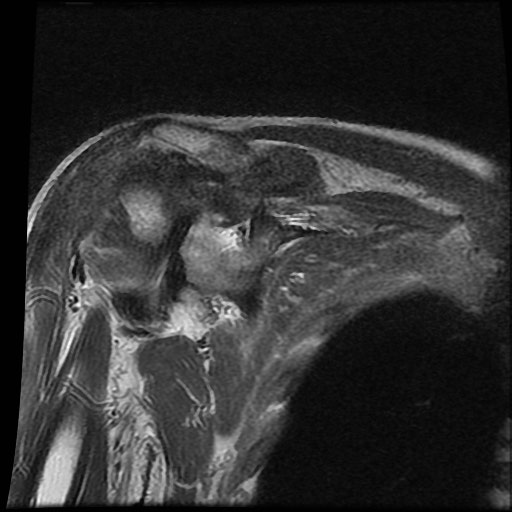

Chuỗi xung T2W

của bệnh nhân bị bệnh khớp do amyloid tại khớp vai.

Các

dấu hiệu bao gồm:

- Sưng nề trong khớp kích thước lớn do

lắng đọng amyloid giảm tín hiệu. - Lan rộng vào khoang dưới mỏm cùng vai và dưới vai.

- Bào mòn lớn tại chỏm xương cánh tay.

Tình trạng sưng nề phần mềm này không nên nhầm lẫn với các hạt cơm (rice bodies) như thấy trong

viêm khớp dạng thấp.